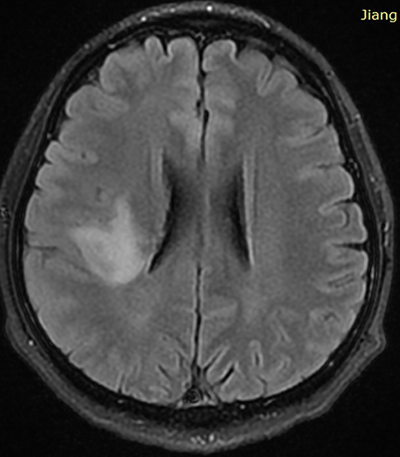

1、40多歲林先生,5個月前突發(fā)左側(cè)面部麻木,隨之出現(xiàn)左上肢麻木由左手向左肩發(fā)射及下肢麻木,經(jīng)檢查發(fā)現(xiàn)右島葉占位,頭顱MRS提示腫瘤性病變(低級別膠質(zhì)瘤)

Q(1):患者腦部占位處于運動功能區(qū),在保留運動功能的前提下,手術(shù)能切除多少?

A:目前我還不建議進(jìn)行大范圍的手術(shù)。目前只適合活檢。有兩種方法可以進(jìn)行活檢:采用小型開顱手術(shù)和顯微手術(shù)技術(shù)去除部分腫瘤,然后進(jìn)行組織病理學(xué)檢查;或立體定向活檢,或者,我們也可以在導(dǎo)航和MRI引導(dǎo)下進(jìn)行活檢以明確病變的性質(zhì)。對于到底是腫瘤(類型)或是炎癥,將會給我們一個明確的答案。

建議患者早日做活檢手術(shù),并在做活檢的同時盡可能大范圍的(注意在確定不傷害正常組織的情況下)切除病變組織。手術(shù)切除時建議使用術(shù)中核磁,即手術(shù)進(jìn)行一半左右時,未明確切剩余病變組織的確切定位,術(shù)中患者會接受核磁檢查,然后根據(jù)核磁顯示,繼續(xù)盡可能多的切除病變組織。其余后續(xù)治療,根據(jù)病理結(jié)果,并且在有必要的情況下做基因檢測來制定下一步更適合患者的治療方案。

對于患者的病情,具體的治療方案,只有在病理結(jié)果出來后才能制定,目前有很多臨床前沿研究、臨床試驗用藥、新疫苗注射等,但這些均需要等患者病理結(jié)果及全序列基因檢測(如有需求)結(jié)果后才能制定。

Q(2):根據(jù)膠質(zhì)瘤的特點,如果手術(shù)未能全部切除會容易復(fù)發(fā),且會越發(fā)越重,是否會在手術(shù)后不多久就復(fù)發(fā)?

A:目前尚不確定這是膠質(zhì)瘤,還是僅僅是炎癥。在炎癥的情況下,手術(shù)是禁忌的。如果結(jié)果是腫瘤,則只有在獲得具有分子分化的較終組織病理學(xué)結(jié)果后才能計劃下一步驟。